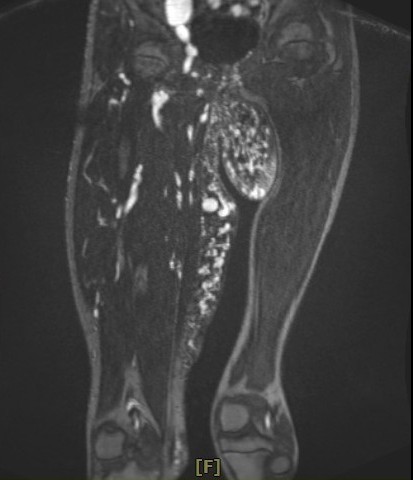

爸爸阿肅表示,小班克從出生時,就發現鼠蹊部處有一點一點如豆子大的紅色凸起點,不會疼痛,直到她三歲時,紅色點點逐漸變大;七歲時,開始感到紅腫疼痛,而且動靜脈血管畸形及微血管畸形開始擴散,遍布右側大腿至臀部,並腫脹得比左大腿還要粗上兩倍。

其中動靜脈血管畸形腫瘤已成為拳頭大小,垂掛在鼠蹊部與右腿間,已經影響到如廁及行動。而右臀部下方因為摩擦產生了小傷口,儘管擦了當地醫師開立的藥膏,傷口在走路時的反覆摩擦下,卻始終無法癒合。爸爸心疼的說,小班克出生後就因為雙腿間的腫瘤及覆蓋在右側大腿上的大面積「紅色胎記」,讓她的成長過程相對辛苦,不捨孩子的堅強,對於小班克也會給予特別多的關愛。

李俊達主任表示,小班克除了腿間的動靜脈畸形瘤,在下腹部、鼠蹊部、大腿大部分是動靜脈畸形,也是造成右大腿腫大的原因。而大腿深部的動脈與靜脈連接在一起,加上包覆大腿皮膚表層的微血管畸形面積很大,若使用雷射方式移除,得進行十次以上的雷射手術,還可能引起大出血;另一種治療方式則是使用栓塞手術,但可能會造成皮膚潰爛或引起併發症,若要全部移除是較為困難。